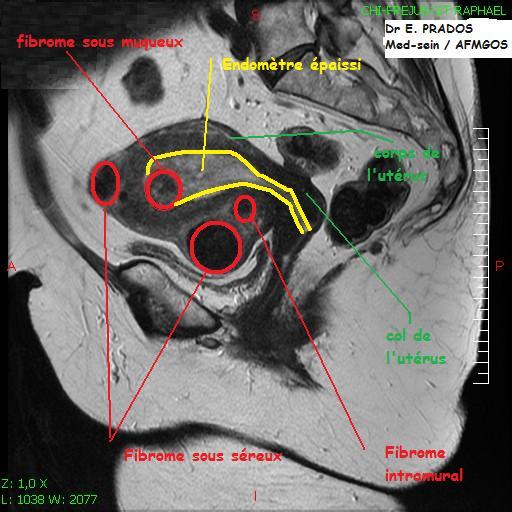

En effet, si les fibromes sous-séreux ne semblent pas entraver la fertilité féminine, d'autres types, comme les fibromes sous-muqueux peuvent nécessiter une prise en charge chirurgicale par hystéroscopie, voire laparotomie ou cœlioscopie selon l'importance de leur composante. Les fibromes sous-muqueux et sous-séreux se développent à partir d'une structure en forme de tige, dépassant parfois de l'utérus dans la région pelvienne

Les fibromes pendant la grossesse peuvent augmenter le risque de : Travail prématuré Un fibrome qui grossit beaucoup pendant la grossesse peut être douloureux En effet, si les fibromes sous-séreux ne semblent pas entraver la fertilité féminine, d'autres types, comme les fibromes sous-muqueux peuvent nécessiter une prise en charge chirurgicale par hystéroscopie, voire laparotomie ou cœlioscopie selon l'importance de leur composante.

FIBROMES UTERINS PLACE DE LEMBOLISATION DR KUHL Radiologue. S'il grossit durant la grossesse, il peut également causer des douleurs et des contractions prématurées Mais les fibromes interstitiels ou les sous-séreux peuvent avoir une incidence sur le déroulement de la grossesse en cas de nécrobiose ou de torsion de fibrome sous séreux pédiculé